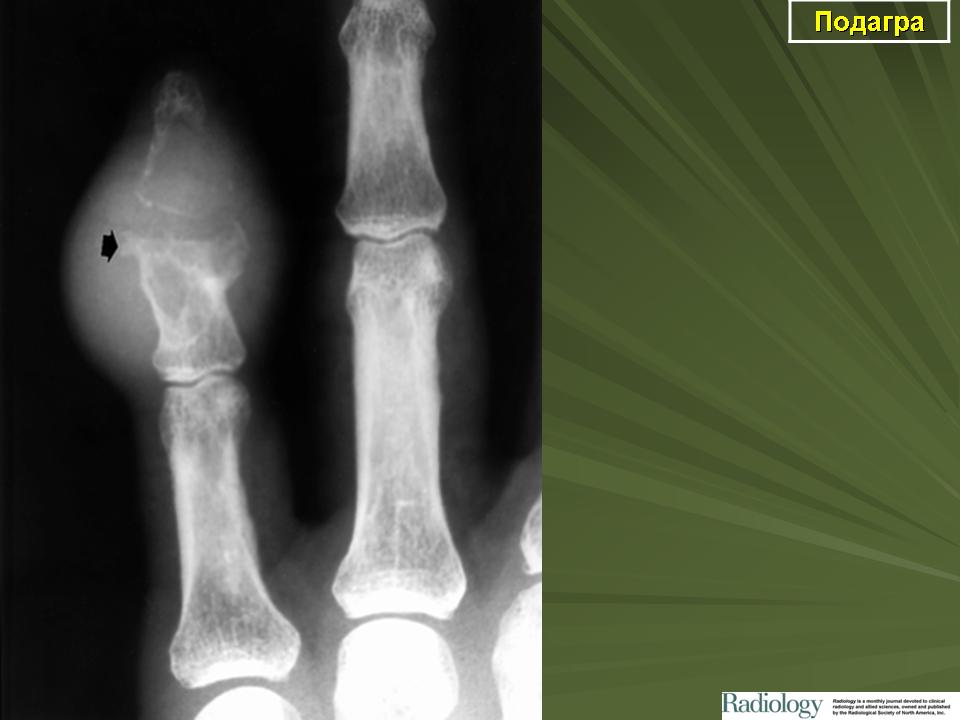

Рентгенологические проявления при подагре впервые описаны G. Huber в 1896 г. Позднее было проведено множество исследований, которые показали, что на ранней стадии болезни не существует каких-либо характерных изменений. Затем на рентгенограммах появляются признаки деструкции костей и хряща, обусловленные отложением кристаллов урата натрия в субхондральной кости.

Более поздней является классификация, предложенная М. Cohen, В. Emmerson (1994), согласно которой к основным рентгенологическим признакам при подагре относят следующие:

• в мягких тканях - уплотнения;

• эксцентрическая затемненность, обусловленная тофусами;

• кости (суставы) - суставная поверхность отчетливо представлена;

• юкстаартикулярный остеопороз отсутствует;

• эрозии (пробойник, краевой склероз).